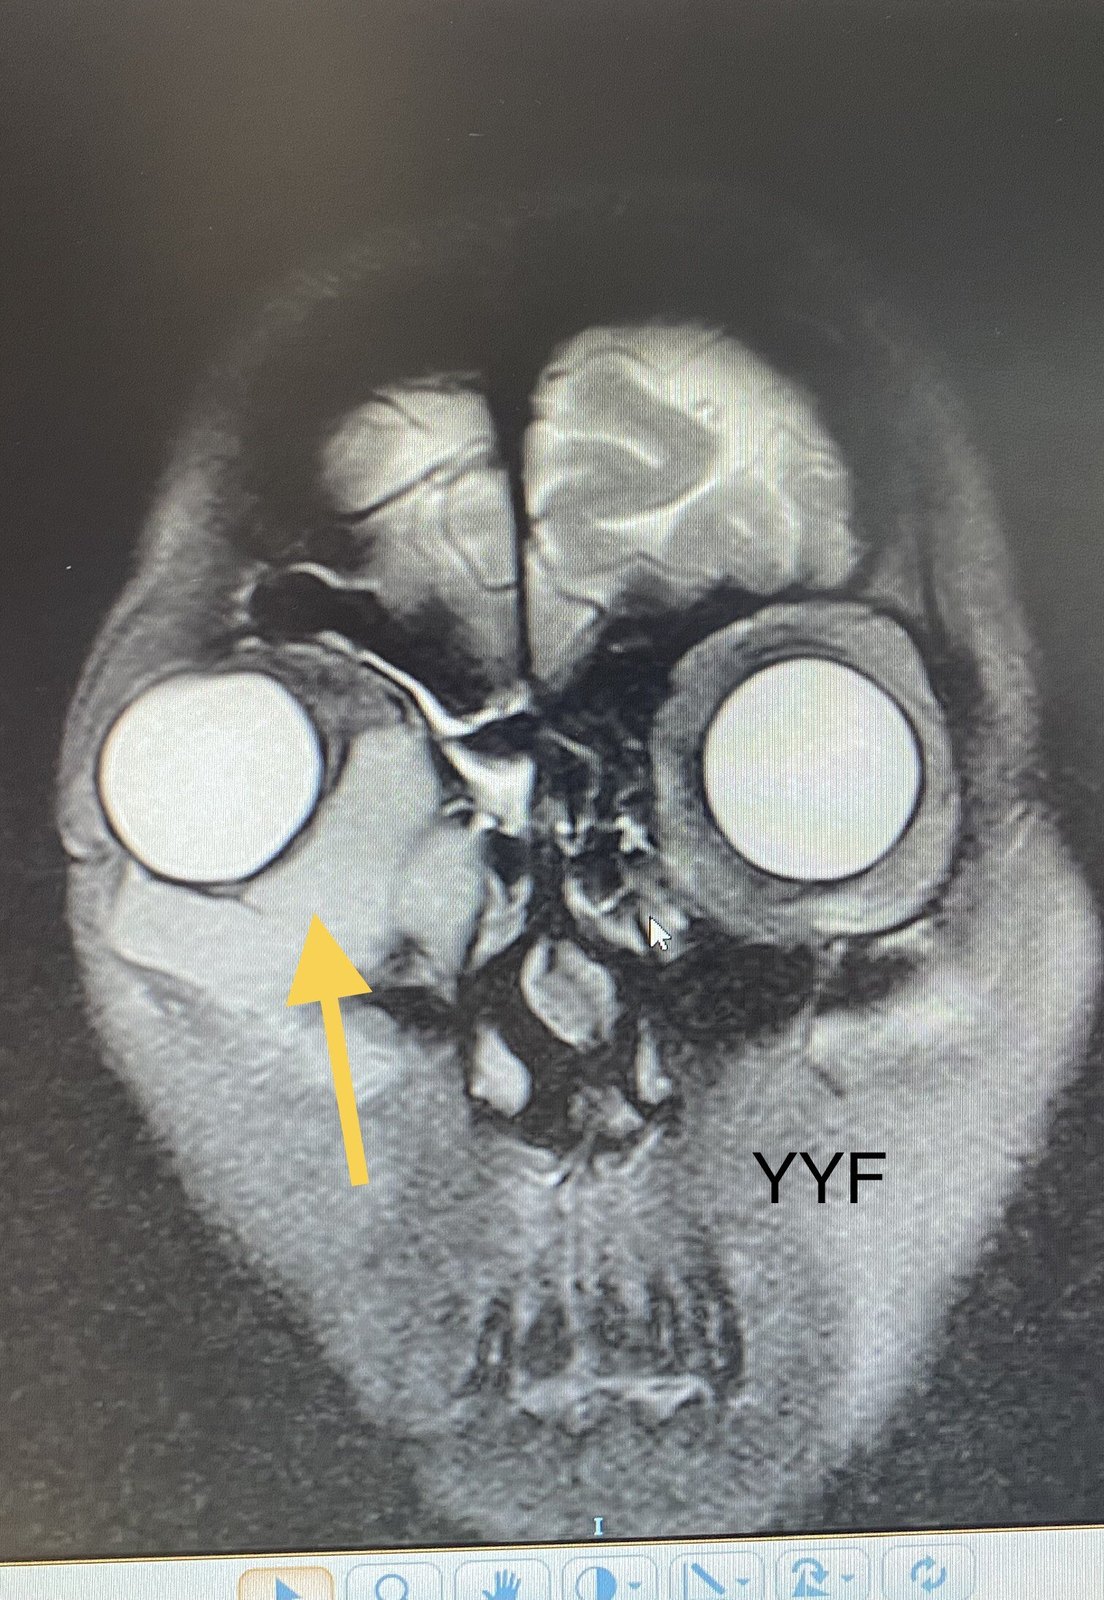

【泪器疾病讨论】早期曾被误诊的泪囊肿瘤 [病例帖]

肿物位于泪囊区,有"炎症"表现,又是女性患者(泪道阻塞性疾病女性更好

ct显示病变以泪囊区为主,但已经超越泪囊仔细分析疾病的发病特点和